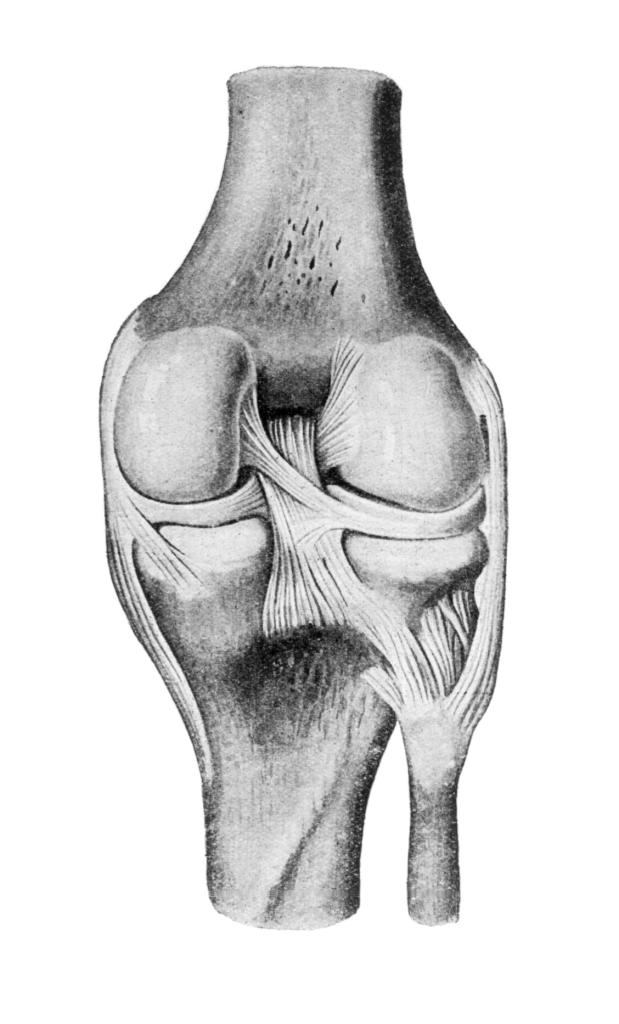

Рисунки Суставов: Анатомические Иллюстрации